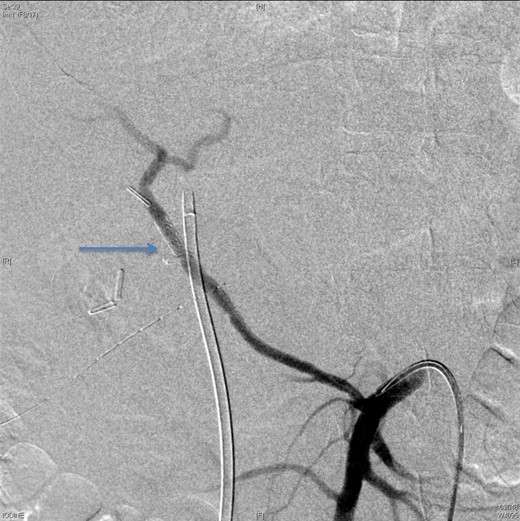

Upon presentation to our center, the patient was febrile (38.9°C) and complained of a left upper limb pain and swelling. The surgical drain was draining a mixture of bile and blood. His WBC count was 14 × 109/l, total bilirubin 35 µmol/l and the direct bilirubin 21 µmol/l. A duplex ultrasound of the upper limb revealed a left brachial vein thrombosis. Hematology was consulted, and a diagnosis of acute upper limb venous thrombosis was established. Owing to the presence of blood in the drain, he was kept on the maximum prophylactic dose of unfractionated heparin. A CT angiography of the abdomen showed two collections, one at the surgical bed near the drain, and the other was subcapsular below the left lateral lobe of the liver, as well as an aneurysm of the replaced right hepatic artery with an active bleeding blush (Fig. 1). The patient was immediately referred for an angiography, which confirmed the CT scan findings (Fig. 2). An arterial stent was inserted at the location of the aneurysm (Fig. 3), and a pigtail drain was inserted to drain any residual collection. An ERCP was also performed, which revealed a Strasberg Class D injury, and a plastic biliary stent was inserted. After the angio-stent insertion and stabilization of the patient, heparin infusion was started. Five days later he developed hematemesis and melena with a significant drop in his Hb to 2 g/l, and his total bilirubin became 183 μmol/l of which 91 μmol/l is direct. A gastroscopy was performed and showed hemobilia (bleeding from the ampulla of Vater). Subsequent angiography demonstrated a leak of contrast just above the arterial stent; hence, a further stent was placed to cover that area of the aneurysm. Similar symptoms reoccurred a week later, and a new angiography showed a new aneurysm from the left proper hepatic artery. A percutaneous thrombin injection of the aneurysm was performed as the bleeding branch was unreached via direct angiography and was filling in retrograde perfusion. During recovery a chest spiral CT was performed, which revealed the diagnosis of a bilateral segmental pulmonary embolism. Heparin infusion with low targets of partial thromboplastin time of 50–60 was started.

An angiographic scan showed stent in the replaced right hepatic artery.